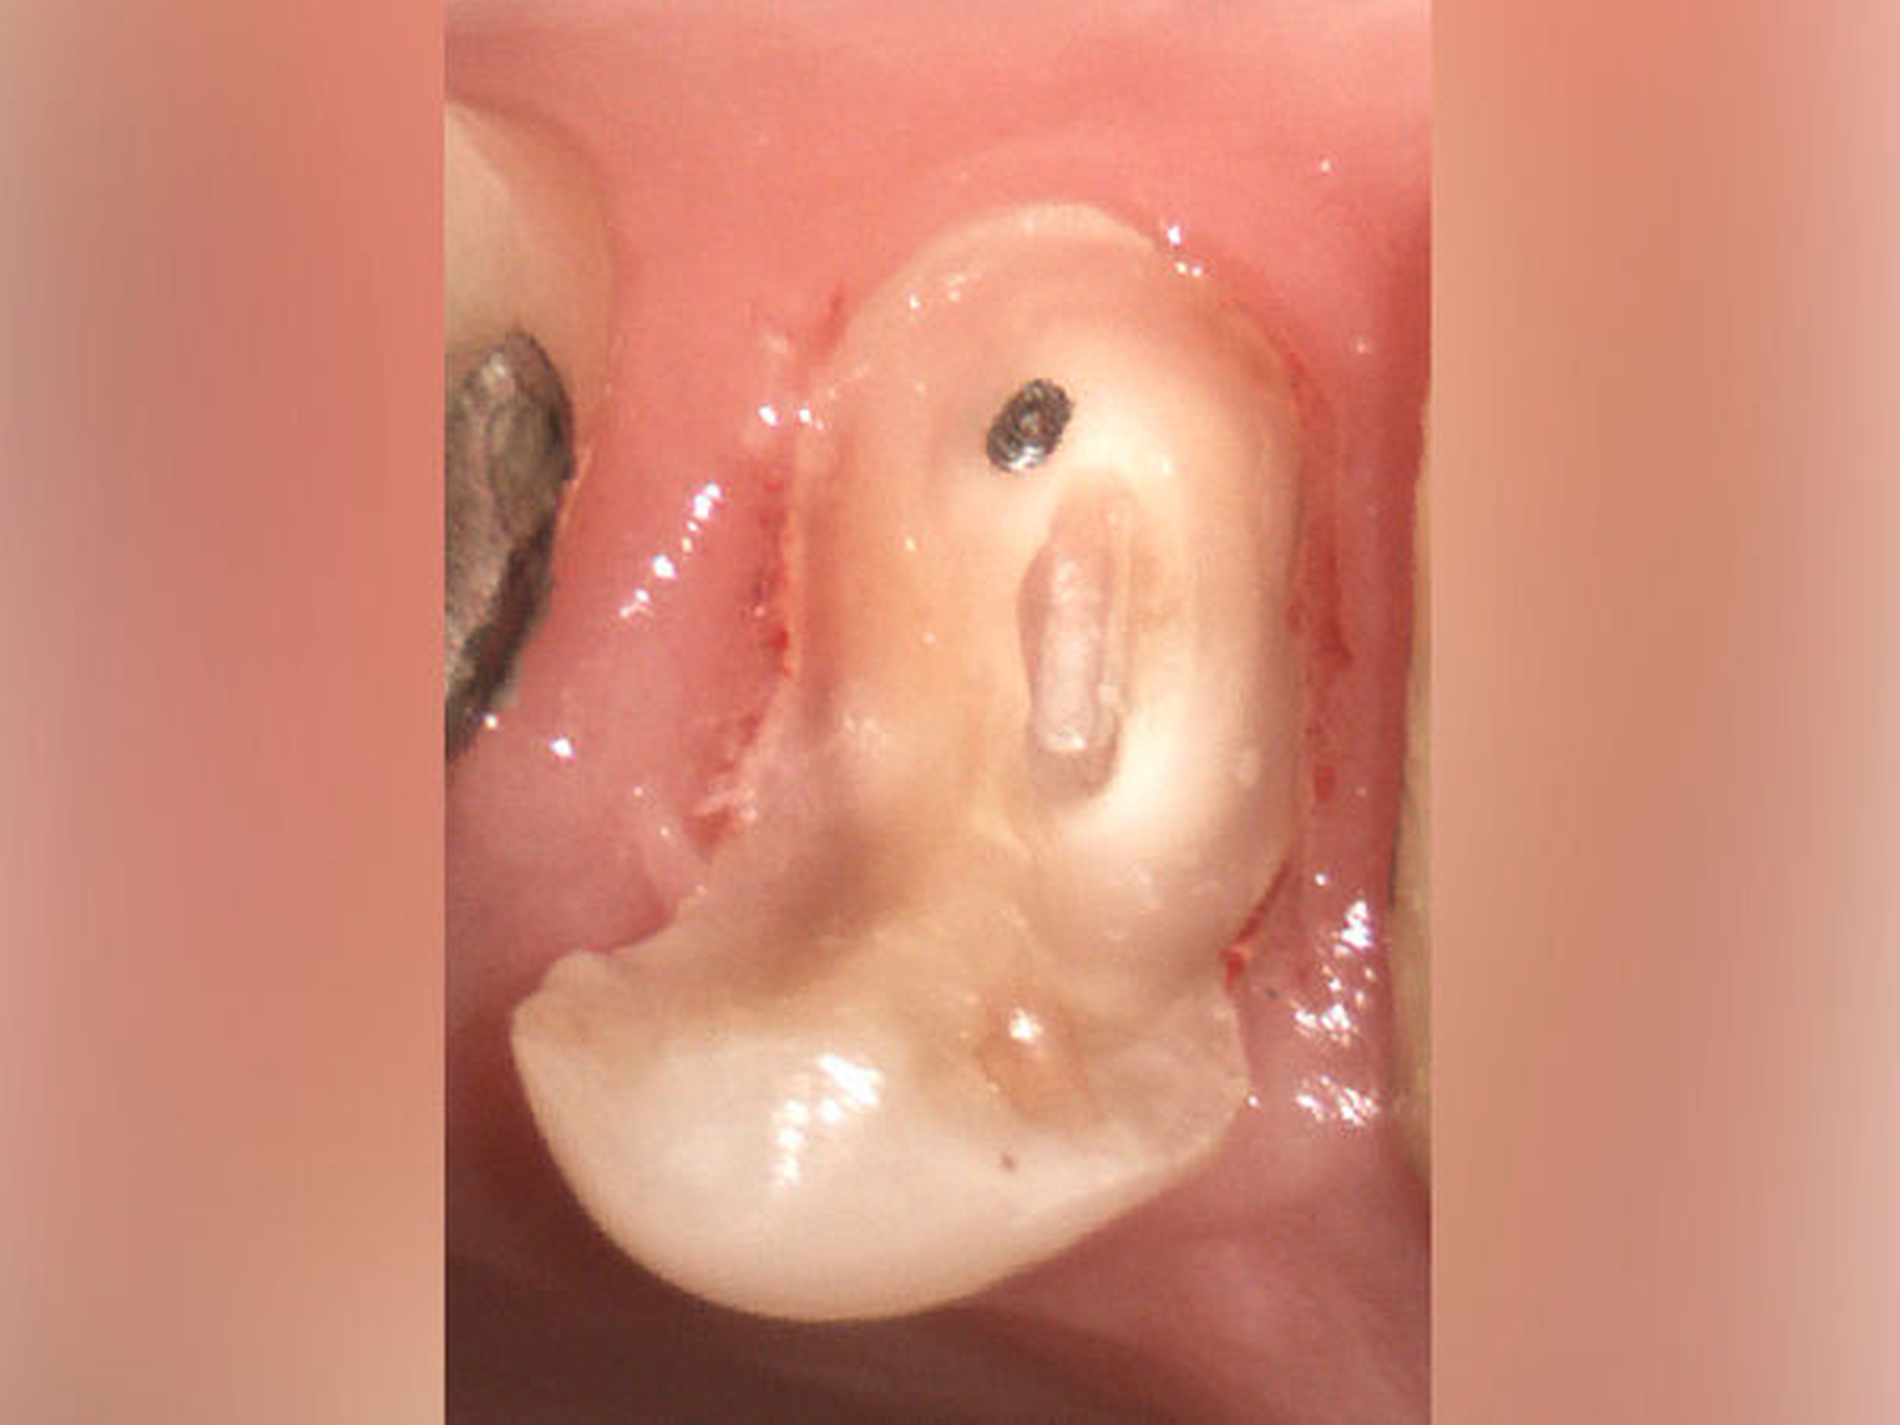

Der Patient stellte sich mit rezidivierenden Beschwerden am Zahn 45 nach einer vor Jahren abgeschlossenen Wurzelkanalbehandlung vor. Die Allgemeinanamnese war unauffällig. Die Schmerzsymptomatik ließ sich auf den Zahn 45 bei positivem Perkussionsreiz lokalisieren. Der approximale Kontaktpunkt distal zum Zahn 46 fehlte. Distal fiel ein pathologischer Sondierungswert von 4 mm auf. Eine Blutung ließ sich bei passiver Messung auslösen und begründete eine plaqueinduzierte Gingivitis.

Auf der intraoralen Röntgenaufnahme lagen eine unvollständige Wurzelkanalfüllung und eine apikale Aufhellung am Zahn 45 vor. Apikal ist auf der Röntgenaufnahme kein Wurzelkanal erkennbar. Die zu kurze Wurzelkanalfüllung deutete auf eine apikale Blockade von eingepresstem Debris oder eine Stufenpräparation hin (Abbildung 14). Als seltene anatomische Variation war eine apikale Aufteilung in zwei Wurzelkanäle in Betracht zu ziehen, so dass die Nutzung einer optischen Vergrößerung mit koaxialer Lichtzufuhr als Hilfsmittel empfehlenswert erschien. Die apikale Wurzelkrümmung ließ einen gleichmäßigen großen Krümmungsradius vermuten. Bei lateralen Aufhellungen ist mit einem lateralen Foramen apicale oder einer Wurzelkanalaufteilung zu rechnen, so dass in diesem Fall die apikale Erweiterung und der Verschluss eine sehr hohe Schwierigkeit vermuten lassen.